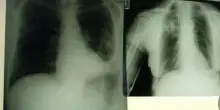

Ictus, da esperti Iss i '6 segnali' per riconoscerlo

(Adnkronos) - In occasione della Giornata mondiale dell'ictus (29 ottobre) il punto sulla malattia, sui sintomi e sull'importanza dell'intervento precoce e della prevenzione